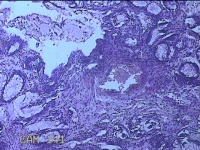

性别

男

年龄

40岁

临床诊断

混合痔

一般病史

反复肛门肿物突出15年。

标本名称

肛门肿物

大体所见

灰白暗红色肿物0.7x0.5x0.2cm一个,表面糜烂。

脱水、透明,浸蜡、脱蜡效果不佳,制片质量差。